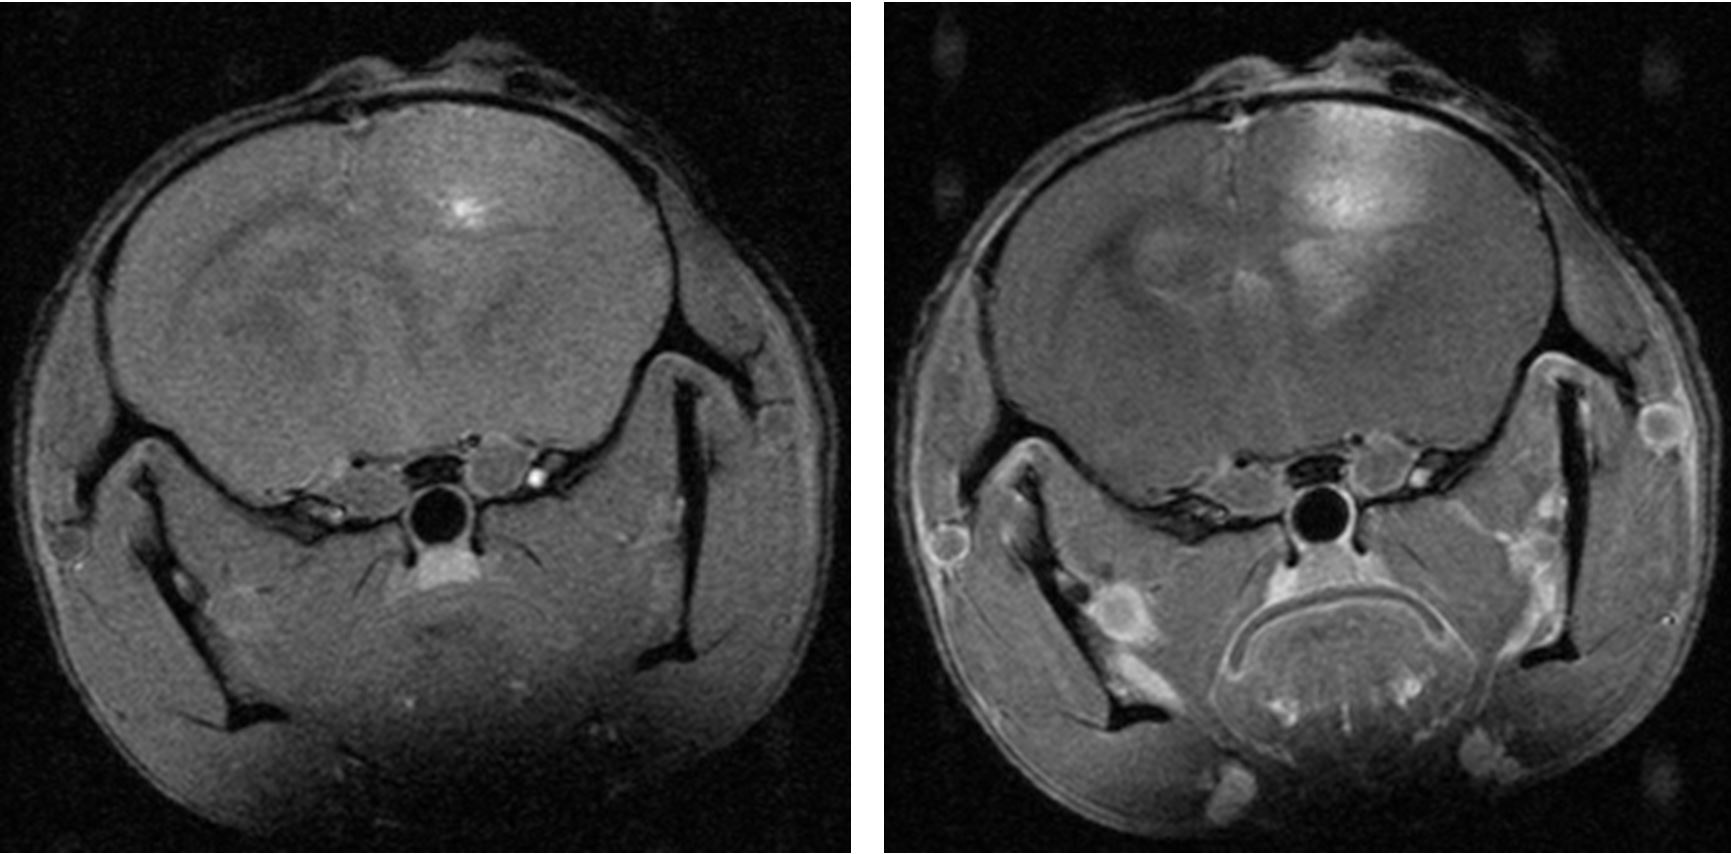

The search for the vulnerabilities of cancer cells

In order to find the vulnerabilities of cancer cells and treat cancer, we need to understand the biology of cancer. How do cancer cells differ from healthy cells, and how do they interact with their environment, or with therapies?